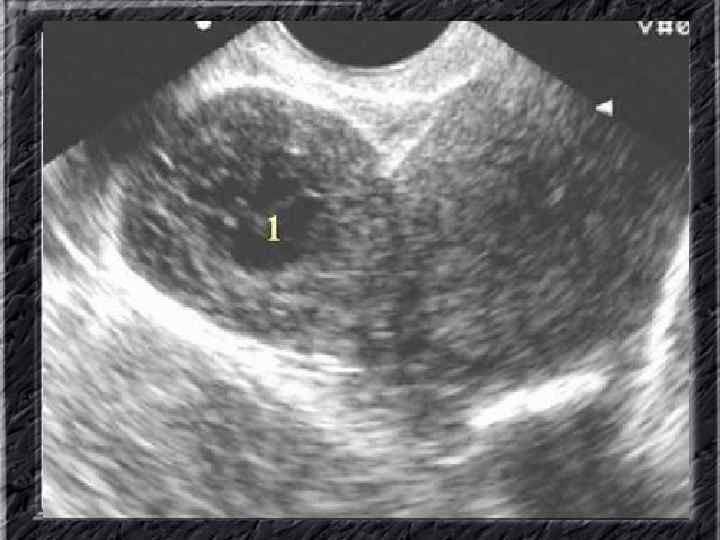

Названия слайдов: • • • Слайд 51. Ультрасонография: интерстициальный и истмический отделы маточной трубы. Слайд 52. Лапароскопия: неизмененная правая маточная труба. Слайд 53. Ультрасонография: многокамерная форма сальпингита. Слайд 54. Лапароскопия: относительно равномерное утолщение маточной трубы при гидросальпинксе. Слайд 55. Лапароскопия: вид маточной трубы при гидросальпинксе. Слайд 56. Гистеросальпингография: неравномерное расширение и деформация маточных труб. Слайд 57. Прервавшаяся трубная беременность: плод; макропрепарат. Слайд 58. Гематосальпингс, развившийся вследствие внутреннего разрыва плодо-вместилища при трубной беременности; макропрепарат. Слайд 59. Лапароскопия: значительное увеличение участка маточной трубы при трубной беременности. Слайд 60. Лапароскопия: скопление крови в полости малого таза в результате трубного аборта.